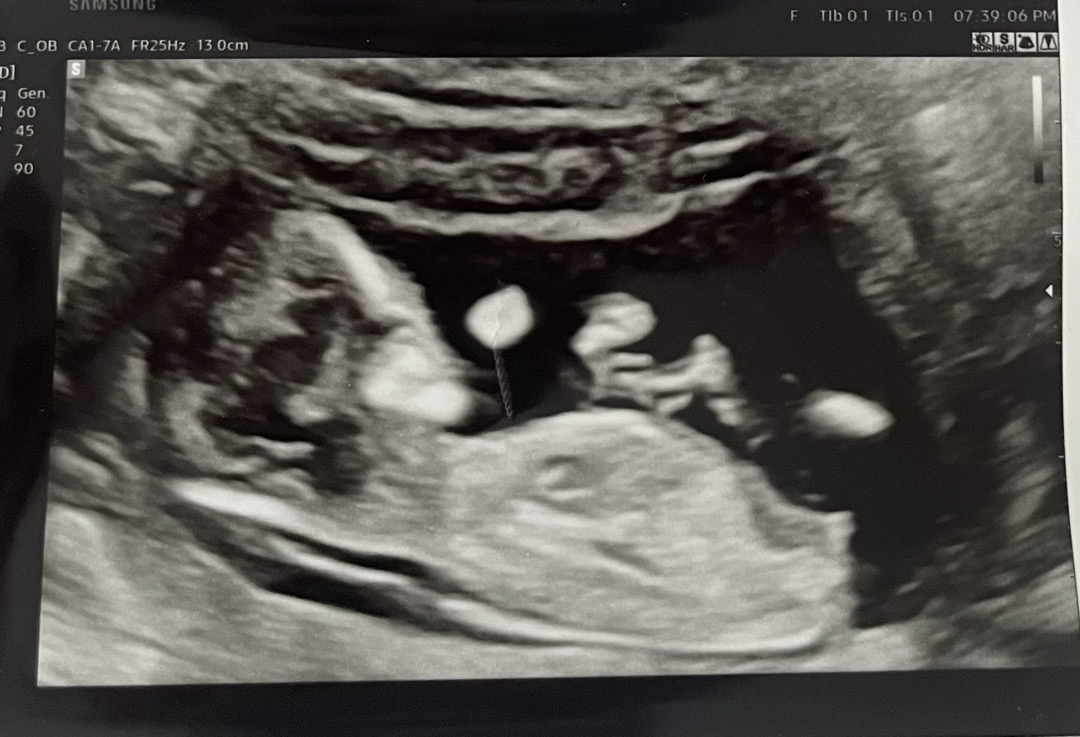

12주차! 각도법 부탁드려용..💕

ㅎㅎ딸이면 좋겠는데.. 의사쌤은 아들같다구 하시네요..🥹